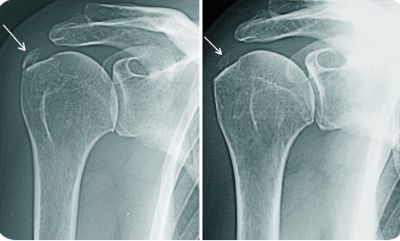

- рентгенографию в 2-х проекциях;

Чаще всего для диагностики периартрита прибегают к рентгенографическому исследованию, УЗИ, МРТ, КТ, артрограмме и клиническому анализу крови. Также проводят дифференциацию с тромбофлебитом вен верхних конечностей, диффузным васкулитом, дерматитом, опоясывающим лишаем и прочими заболеваниями.